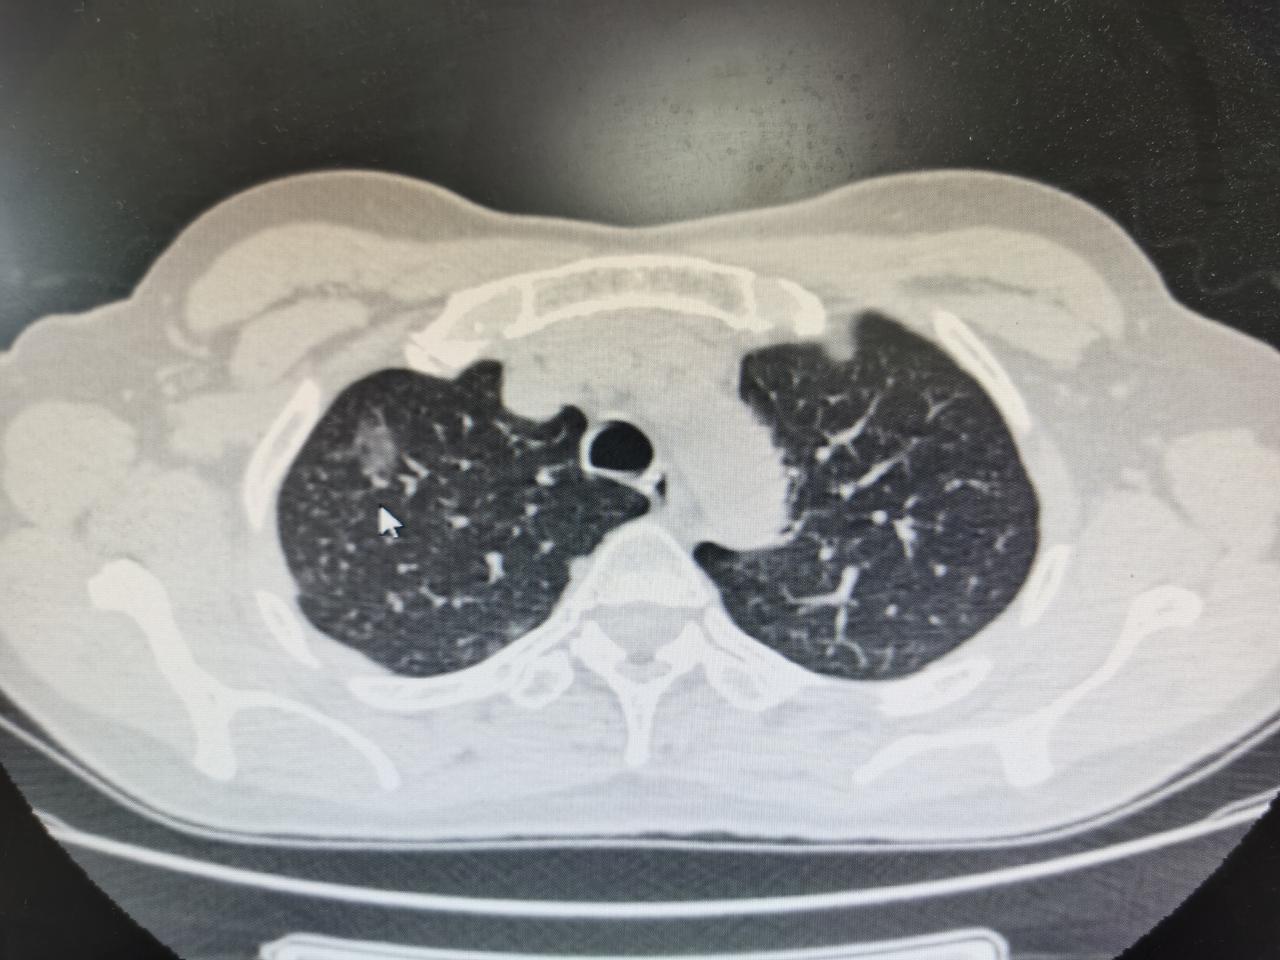

[心]肺结节的6种描述,这次教会你看!会看了不用四处求人! 描述1:边界清 多是良性,不需要治疗,定期复查。 描述2:边界模糊 可能是良性,也可能是恶性,具体需要观察结节的大小形态以及是否有其他症状。 描述3:肺纹理增多 一般是有慢性支气管炎,多见于吸烟者。 描述4:结节有毛刺、分叶状 提示恶性结节的可能性较大。 描述5:肺内淋巴结 一般是慢性炎症所致。 描述6:胸膜粘连 多由炎症、外伤引起,多数情况不用治疗。